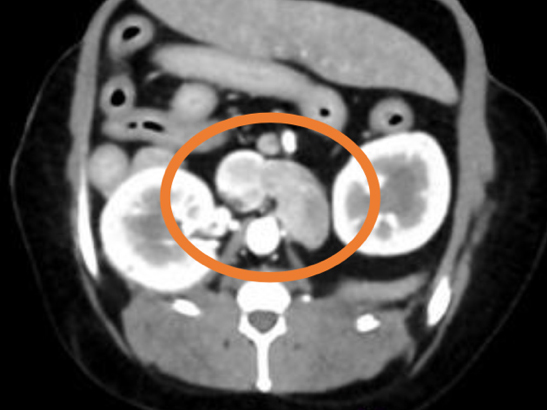

膀胱結石の精査目的で他院にてCT検査を実施したところ、左副腎に腫瘍性病変が認められ、後大静脈への浸潤も確認されました。 これを受けて、手術目的で当院を受診されました。 当院にて褐色細胞腫摘出術を実施し、術後は体調良好であったため、術後4日目に退院されました。

手術前のCT検査にて腫瘍の浸潤・転移チェックを実施

副腎腫瘍の中には、後大静脈などの重要な血管の中に腫瘍が入り込む(血管内浸潤)タイプがあります。このような場合、手術はさらに高度で慎重な対応が求められます。 当院では、術前にCT検査などを用いて正確な病態を把握し、安全に手術を実施する体制を整えております。必要に応じて、外科専門医や麻酔専門医がチームで対応いたします。